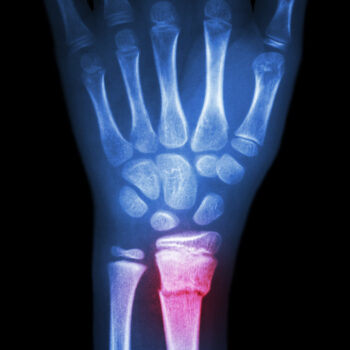

Wrist fractures, breaks or greenstick injuries in children are common and can be pretty traumatic. They generally result from sustaining a fall on an outstretched hand, also known as ‘FOOSH’. Common causes of greenstick fracture or paediatric buckle fracture include falling off gym equipment, skateboards and bicycles.. just to name a few. Unlike adult bones, children tend to “bend” before they break and so all of these types if fractures are stable, they heal quickly and can be treated in a light weight “cast” that is water proof and allows children to get on with their lives like swimming!

Signs and symptoms will vary, depending on the severity of the greenstick fracture. Mild fractures might be mistaken for sprains or bruises. More-severe greenstick fractures may cause an obvious deformity, accompanied by significant pain and swelling. Your hand therapist at Action Rehab will be able to read your xray, assess your injury and treat it appropriately to maximise function. Greenstick or Buckle Fractures are stable, they do not need surgery and they heal quickly with the right care.

Choosing the right hand therapist starts with them being able to read your X-rays and then fabricate the right brace for you. The therapists at Action Rehab are experienced in assessing and reading X-rays.

Greenstick buckle fractures take about 6 weeks to recover but depending on the type of fracture it may heal more quickly. Weirdly Greenstick injuries are not really “breaks” and children’s bones bend before they break.